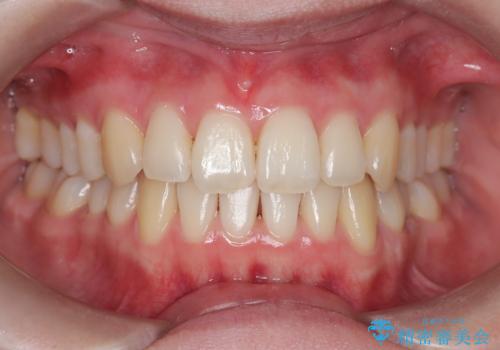

【インビザライン】 前歯の反対咬合を治したい

- なるべく目立たない装置を希望されたためインビザラインにて治療を行いました。

左下5番は先天性欠損のため乳歯は抜歯しインプラントにて欠損補綴しています。